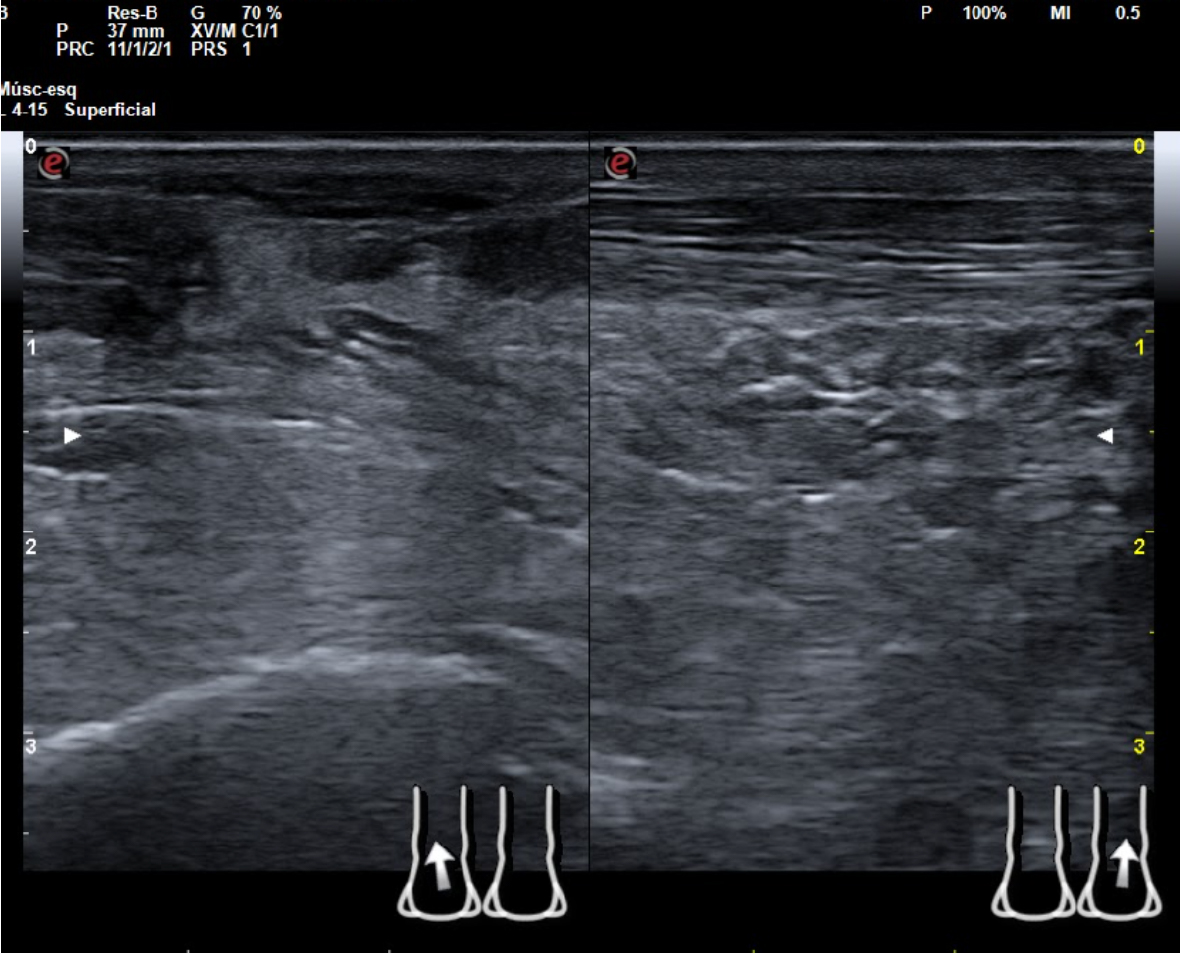

En tendón aquíleo izquierdo se aprecia rotura completa con solución de continuidad de 2 cm localizada a 5,7 cm de su inserción en el calcáneo. Presenta áreas hipoecoicas peritendón que sugieren hematoma secundario. En el aquíleo derecho presenta leve hipoecogenicidad y engrosamiento del tendón sin solución de continuidad que sugiere tendinosis. Importante componente inflamatorio. No datos de TVP. Poplítea y safena externa permeables y compresibles en ambas extremiedades.

Juicio clínico: Rotura completa de tendón de Aquiles izquierdo. Tendinosis aquílea derecha.